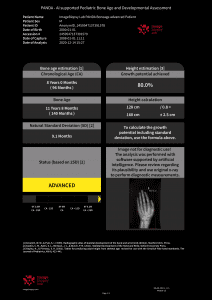

Dr. Richard Ljuhar:IB Lab is aiming to disrupt the way bone and joint diseases are currently being diagnosed. Technologies such as AI-supported software offer a novel way to translate imaging data into structured health information. IB Lab has developed (and certified) a unique MSK-analysis-focused digital workflow platform named IBLAB ZOO. Our deeptech technology is based on state-of-the-art image recognition algorithms and AI, trained on data sets extracted from an accessible image pool of 10 million medical images of various formats. The initial focus of our MSK platform has been on 2D X-ray modules for the knee, hip, hand and spine. The structured information extracted from imaging data enables us not only to disrupt the current workflow by providing standardization and increasing diagnostic accuracy, but also to create new insights into the prediction of disease onset and treatment outcomes.

Dr. Richard Ljuhar: Targeted treatment options ensure shorter periods of suffering, quicker recovery by applying objective assessment/progression measurements and prevention/delay of disease progression, leading to better outcomes. Enhanced and well-structured reports ensure ideal patient communication. MSK diagnoses are often time-consuming and subjective. IB Lab supports radiologists and orthopedists in their daily decision-making with standardized, fast and resource-effective AI-based software solutions for automated measurements on radiographs that accelerate the workflow and improve the time and quality of patient care.